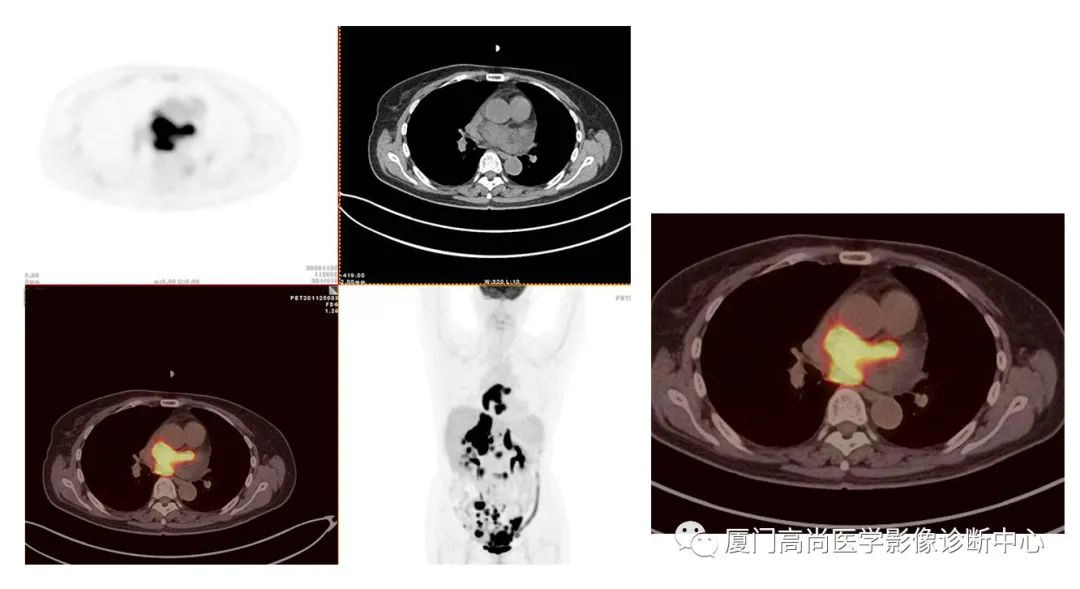

病例2、某女士,62歲,近3個月來自覺消瘦,無其他自覺癥狀,CT發(fā)現(xiàn)雙側(cè)腎上腺增大,性質(zhì)待定,查血各項腫瘤標(biāo)記物均正常,臨床診斷不清,申請做PET/CT檢查

左心房淋巴瘤病灶

右心房淋巴瘤病灶

雙側(cè)腎上腺病灶、膽囊病灶

腹腔淋巴結(jié)腫大

小腸多段淋巴瘤病灶

PET/CT發(fā)現(xiàn) :左心房、右心房見團塊狀FDG攝取增高;雙側(cè)腎上腺增大,F(xiàn)DG攝取增高;膽囊和胃壁結(jié)節(jié)樣FDG攝取增高;小腸多節(jié)段腸壁增厚,F(xiàn)DG攝取增高;腹膜后、腹腔及盆腔多發(fā)淋巴結(jié)腫大,F(xiàn)DG攝取增高;上述考慮為淋巴瘤

經(jīng)腎上腺穿刺活檢 :病理證實為彌漫大B細胞淋巴瘤